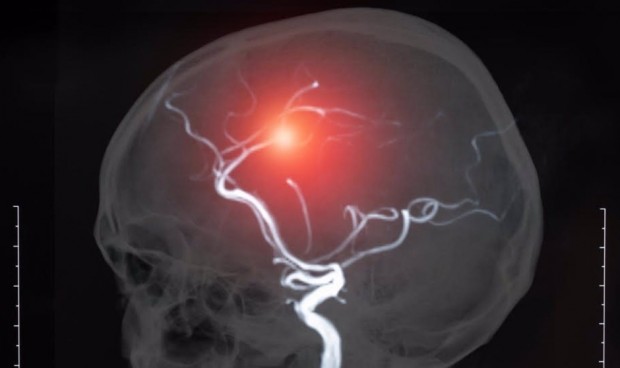

En este sentido, la trombectomía endovascular es un tratamiento no quirúrgico cada vez más utilizado para el accidente cerebrovascular isquémico, en el que se insertan microcatéteres o tubos delgados visibles con rayos X en el coágulo de sangre para disolverlo.

"Una desventaja potencial de este tratamiento, ahora ampliamente utilizado y efectivo, es que el rápido retorno del suministro de sangre a un área que ha estado privada de oxígeno durante un tiempo puede causar daño tisular conocido como lesión por reperfusión", han detallado los expertos.